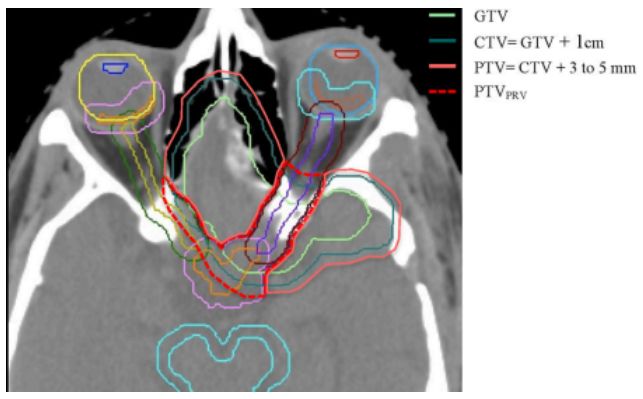

5.中等风险脑膜瘤的放疗结果:NRG Oncology RTOG 0539的第一份临床报告

Intermediate-risk meningioma: initial outcomes from NRG Oncology RTOG 0539.

PMID: 28984517 DOI: 10.3171/2016.11.JNS161170

这是NRG肿瘤学RTOG 0539的第一份临床结果报告,详细描述了肿瘤的主要终点、3年无进展生存期(3-year progression-free survival, 3yPFS)、与预先确定的中危脑膜瘤进行历史对照,并二次评估总体生存率(overall survival, OS)、局部失败和前瞻性评分不良事件(adverse events, AEs)。研究表明,中等风险脑膜瘤患者RT治疗后具有良好的3yPFS,局部失败率低且AEs风险低。

【周川】